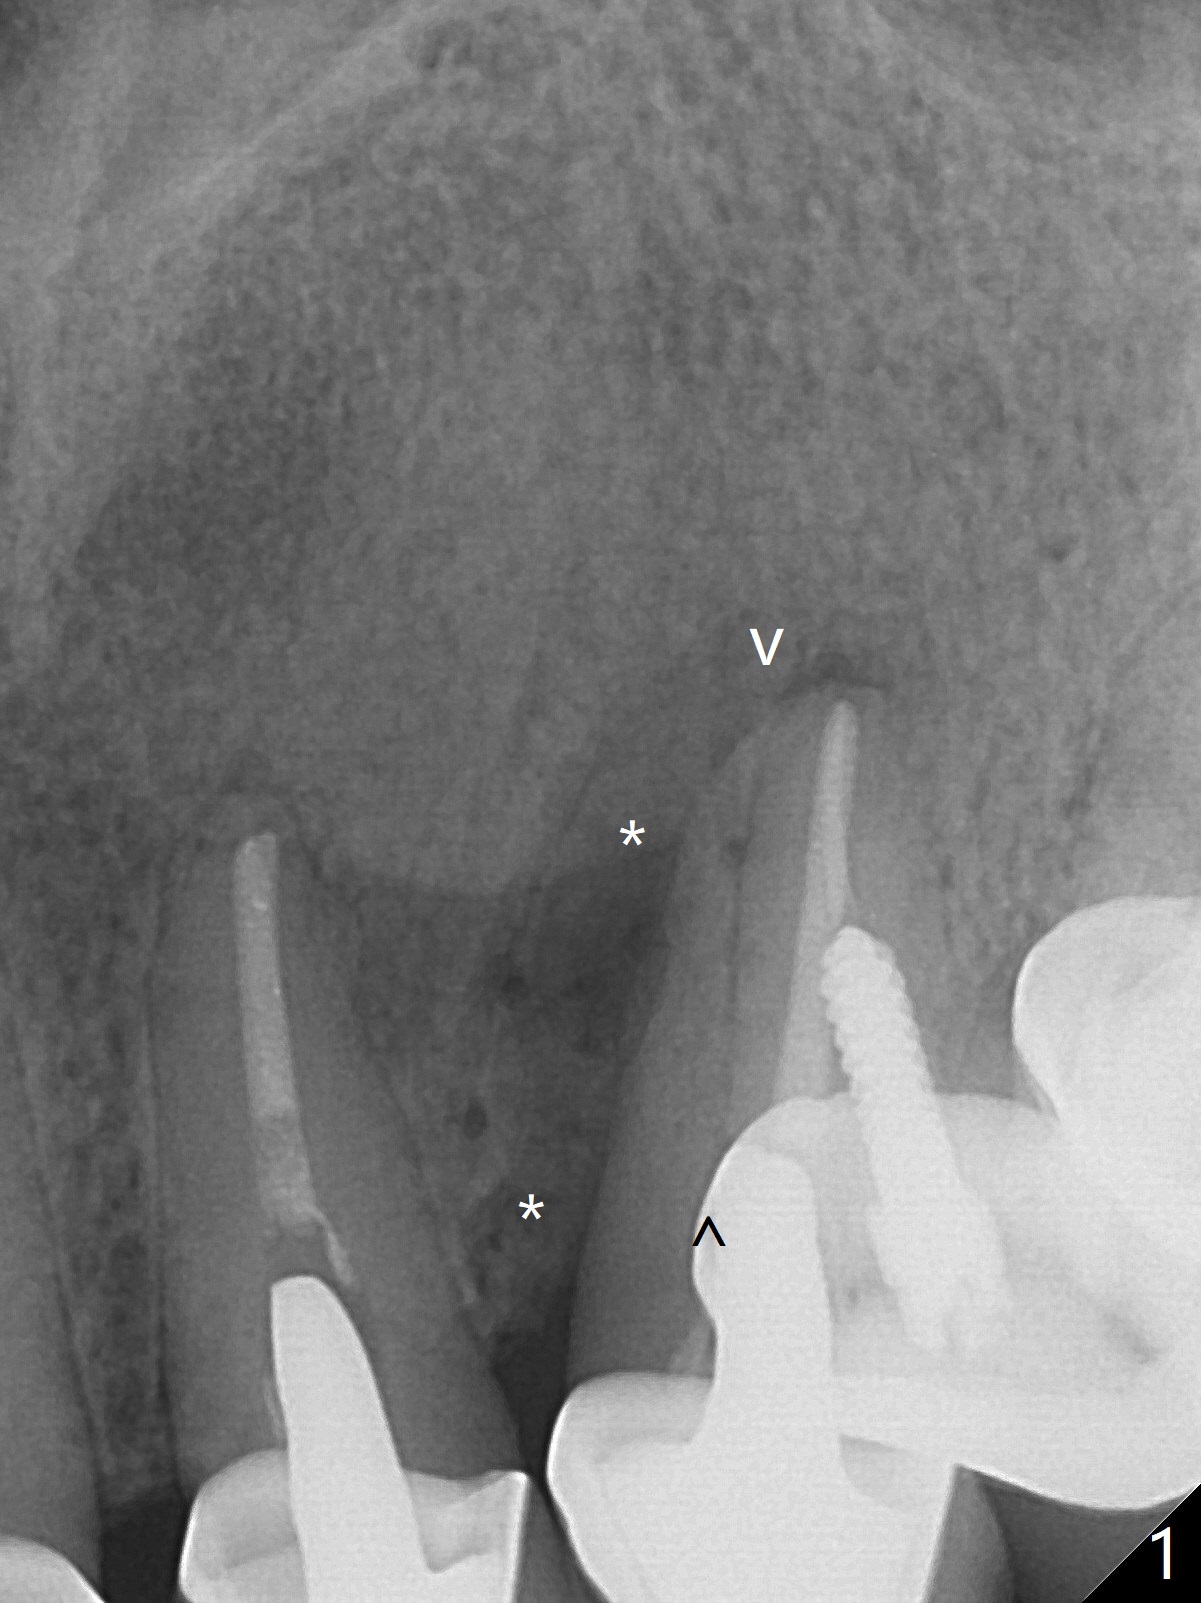

A 52-year-old woman has possible vertical root fracture at #11 (Fig.1 arrowheads (mesial radiolucency: *)) associated with several missing molars. For primary stability, the longest bone-level implant will be placed (Fig.2) with 7 mm in the native bone.